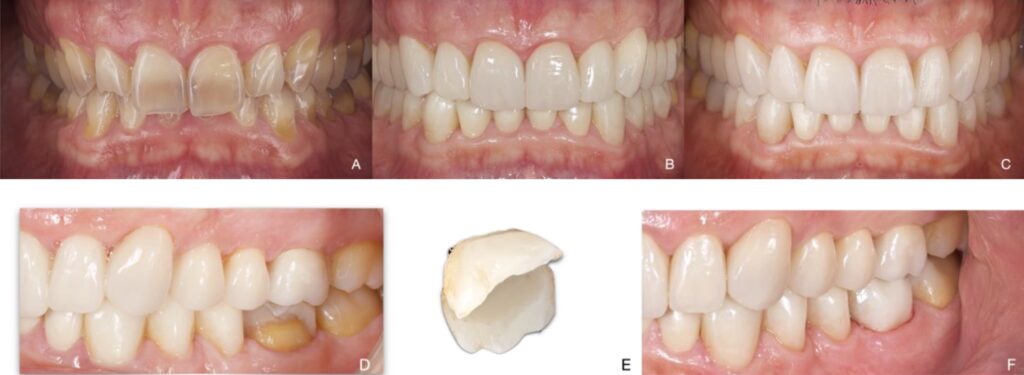

Figure 7. Patient 7. Generalized severe pathological tooth wear (TWES 2.0). (A) Intraoral situation:

edge-to-edge bite and occlusal relationships shown by a patient with severely worn anterior teeth.

We can observe a class III malocclusion that was solved with an extraction of the lower right central

incisor (4.1) associated with a complete orthodontic treatment prior to the restorative phase.

(B) Occlusion after orthodontic treatment (the extraction of 4.1 was necessary to alleviate crowding).

Restorative treatment was performed with composites in the mandible and feldesphatics ceramics in

the maxilla. The aesthetic and functional improvement is noteworthy. (C) Resolution of the fracture

with a direct composite resin. Note the maintenance of occlusal contact relationships and periodontal

health at 5 years. (D) Initial orthopantomography. (E) Follow-up at 4 years. Fracture of the incisal

edge of the ceramic veneer on 2.1 due to trauma with a glass bottle. (F) Final orthopantomography

showing direct stamped composite resin supplementation in the posteroinferior sectors (3.3–3.7 and

4.3–4.7) and feldesphatics veneers from 1.5 to 2.5 and on 4.2, 3.1 and 3.2.

Figure 8. Patient 8. Generalized severe pathological tooth wear (TWES 2.0). (A) Intraoral situation:

deep overbite and occlusal relationships shown by a patient with severely worn anterior teeth and

severe tetracycline staining. (B) Occlusion after restorative treatment from 1.6 to 2.6 with feldsphatic

veneers in the maxilla and from 3.2 to 4.2. CAD-CAM indirect nanoceramic resins were used for the

palatal veneers (1.3–2.3) and in the mandible (occlusal–vestibular from 3.3 to 3.7 and from 4.3 to 4.7).

From a patient perspective, the aesthetic and functional improvement is outstanding. (C) Follow-up

photograph at 5 years. Note the maintenance of occlusal contact relationships and periodontal health,

although there is recession in 1.3 and 1.2. (D) Fracture of CAD-CAM composite nanoceramic resin in

3.6 at 4 years. (E) Detail of the fractured fragment. (F) Re-bonding of the fractured fragment.